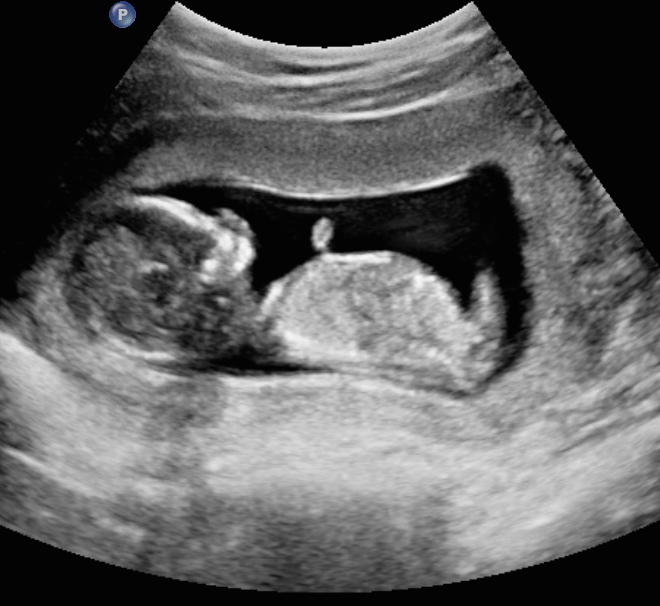

13 weeks 3 days. My first ultrasound. Tech wouldn't take a guess. Id love to know if any of you think girl or boy!!Attachment 25012Attachment 25013Attachment 25014

I'm sorry, I don't see a nub, but will give a boy skull guess just for fun! (not reliable!)

Nope they did a good job keeping that nub hidden from view on the angles they chose.

Not seeing any clue, sorry...